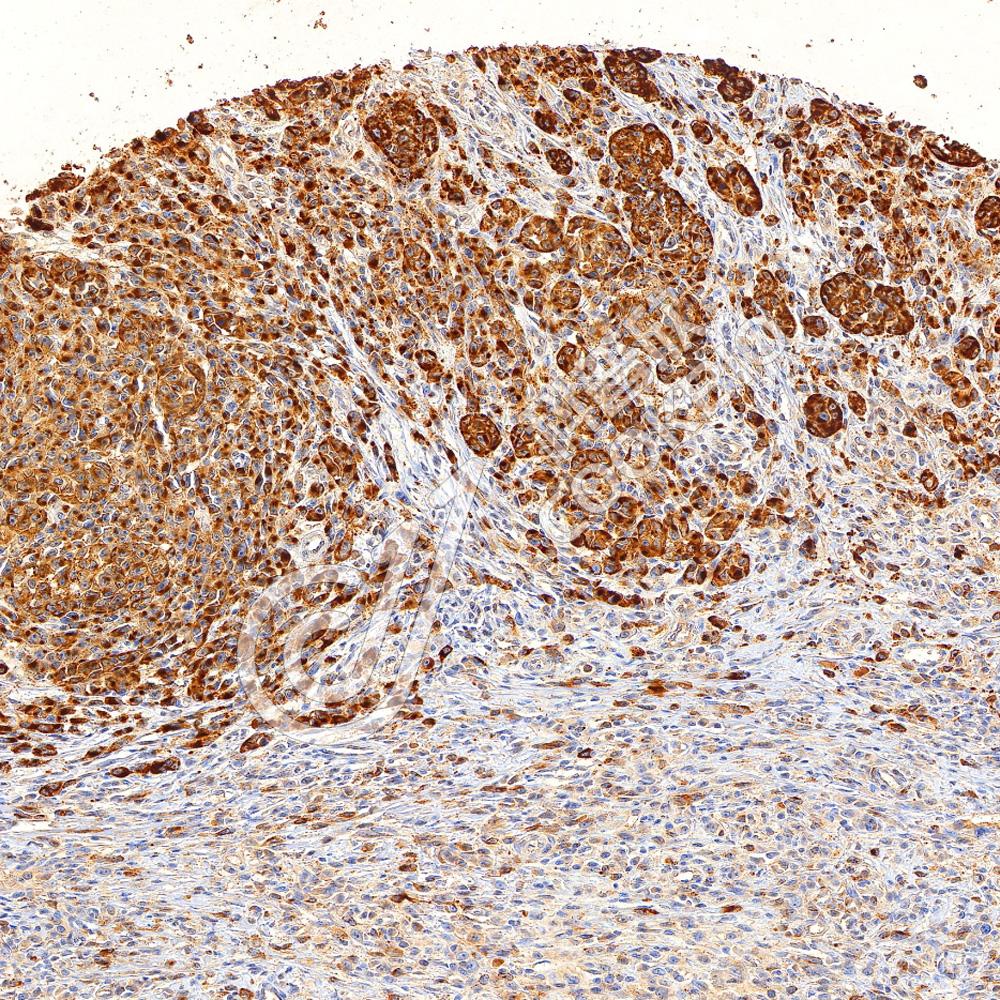

IHC检测Myeloperoxidase蛋白(货号 K2360048).

样品: 人扁桃体, 4%多聚甲醛 (货号KSG1101) 固定12-24小时.

抗原修复: 柠檬酸抗原修复液(干粉, pH 6.0) (KSG1201), 高压锅均匀喷气计时2分钟.

—抗: 1: 1000稀释, 4℃ 孵育过夜.

二抗: S-vision免疫组化多聚二抗(山羊抗小鼠), 即用型(货号KB3903), 室温孵育20分钟.